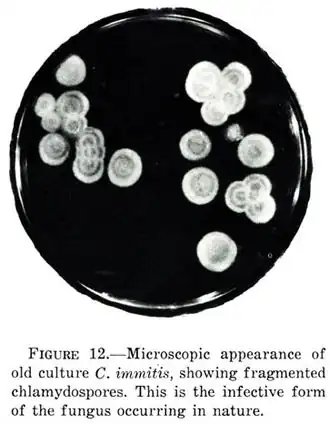

- 'chlamydosporen' zijn ongeslachtelijke rustsporen van gisten. Deze dikwandige sporen kunnen ongunstige omstandigheden, zoals droge of hete seizoenen, overleven. Chlamydosporen hebben een ronde vorm en een glad oppervlak. Ze zijn meercellig, waarbij de cellen via poriën in het septum met elkaar in verbinding staan.

Chlamydosporen van Coccidioides immitis

Chlamydosporen van Coccidioides immitis -

Dehiscentie

Het laatste onderscheidende kenmerk is de 'dehiscentie', het proces waarin de sporen zich afscheiden. Dehiscentie kan op twee verschillende manieren geschieden. Bij de 'schizolytische' varianten vormt zich tussen de sporen een dubbele scheidingswand met centraal gelegen middellamellen. Als deze wand uiteenvalt worden de sporen losgelaten. Bij rhexolytische dehiscentie, zoals bij soorten van het geslacht Coccidioides, worden de sporen uitwendig verbonden door een celwand die op een gegeven moment degenereert, waardoor de conidiosporen vrij komen.